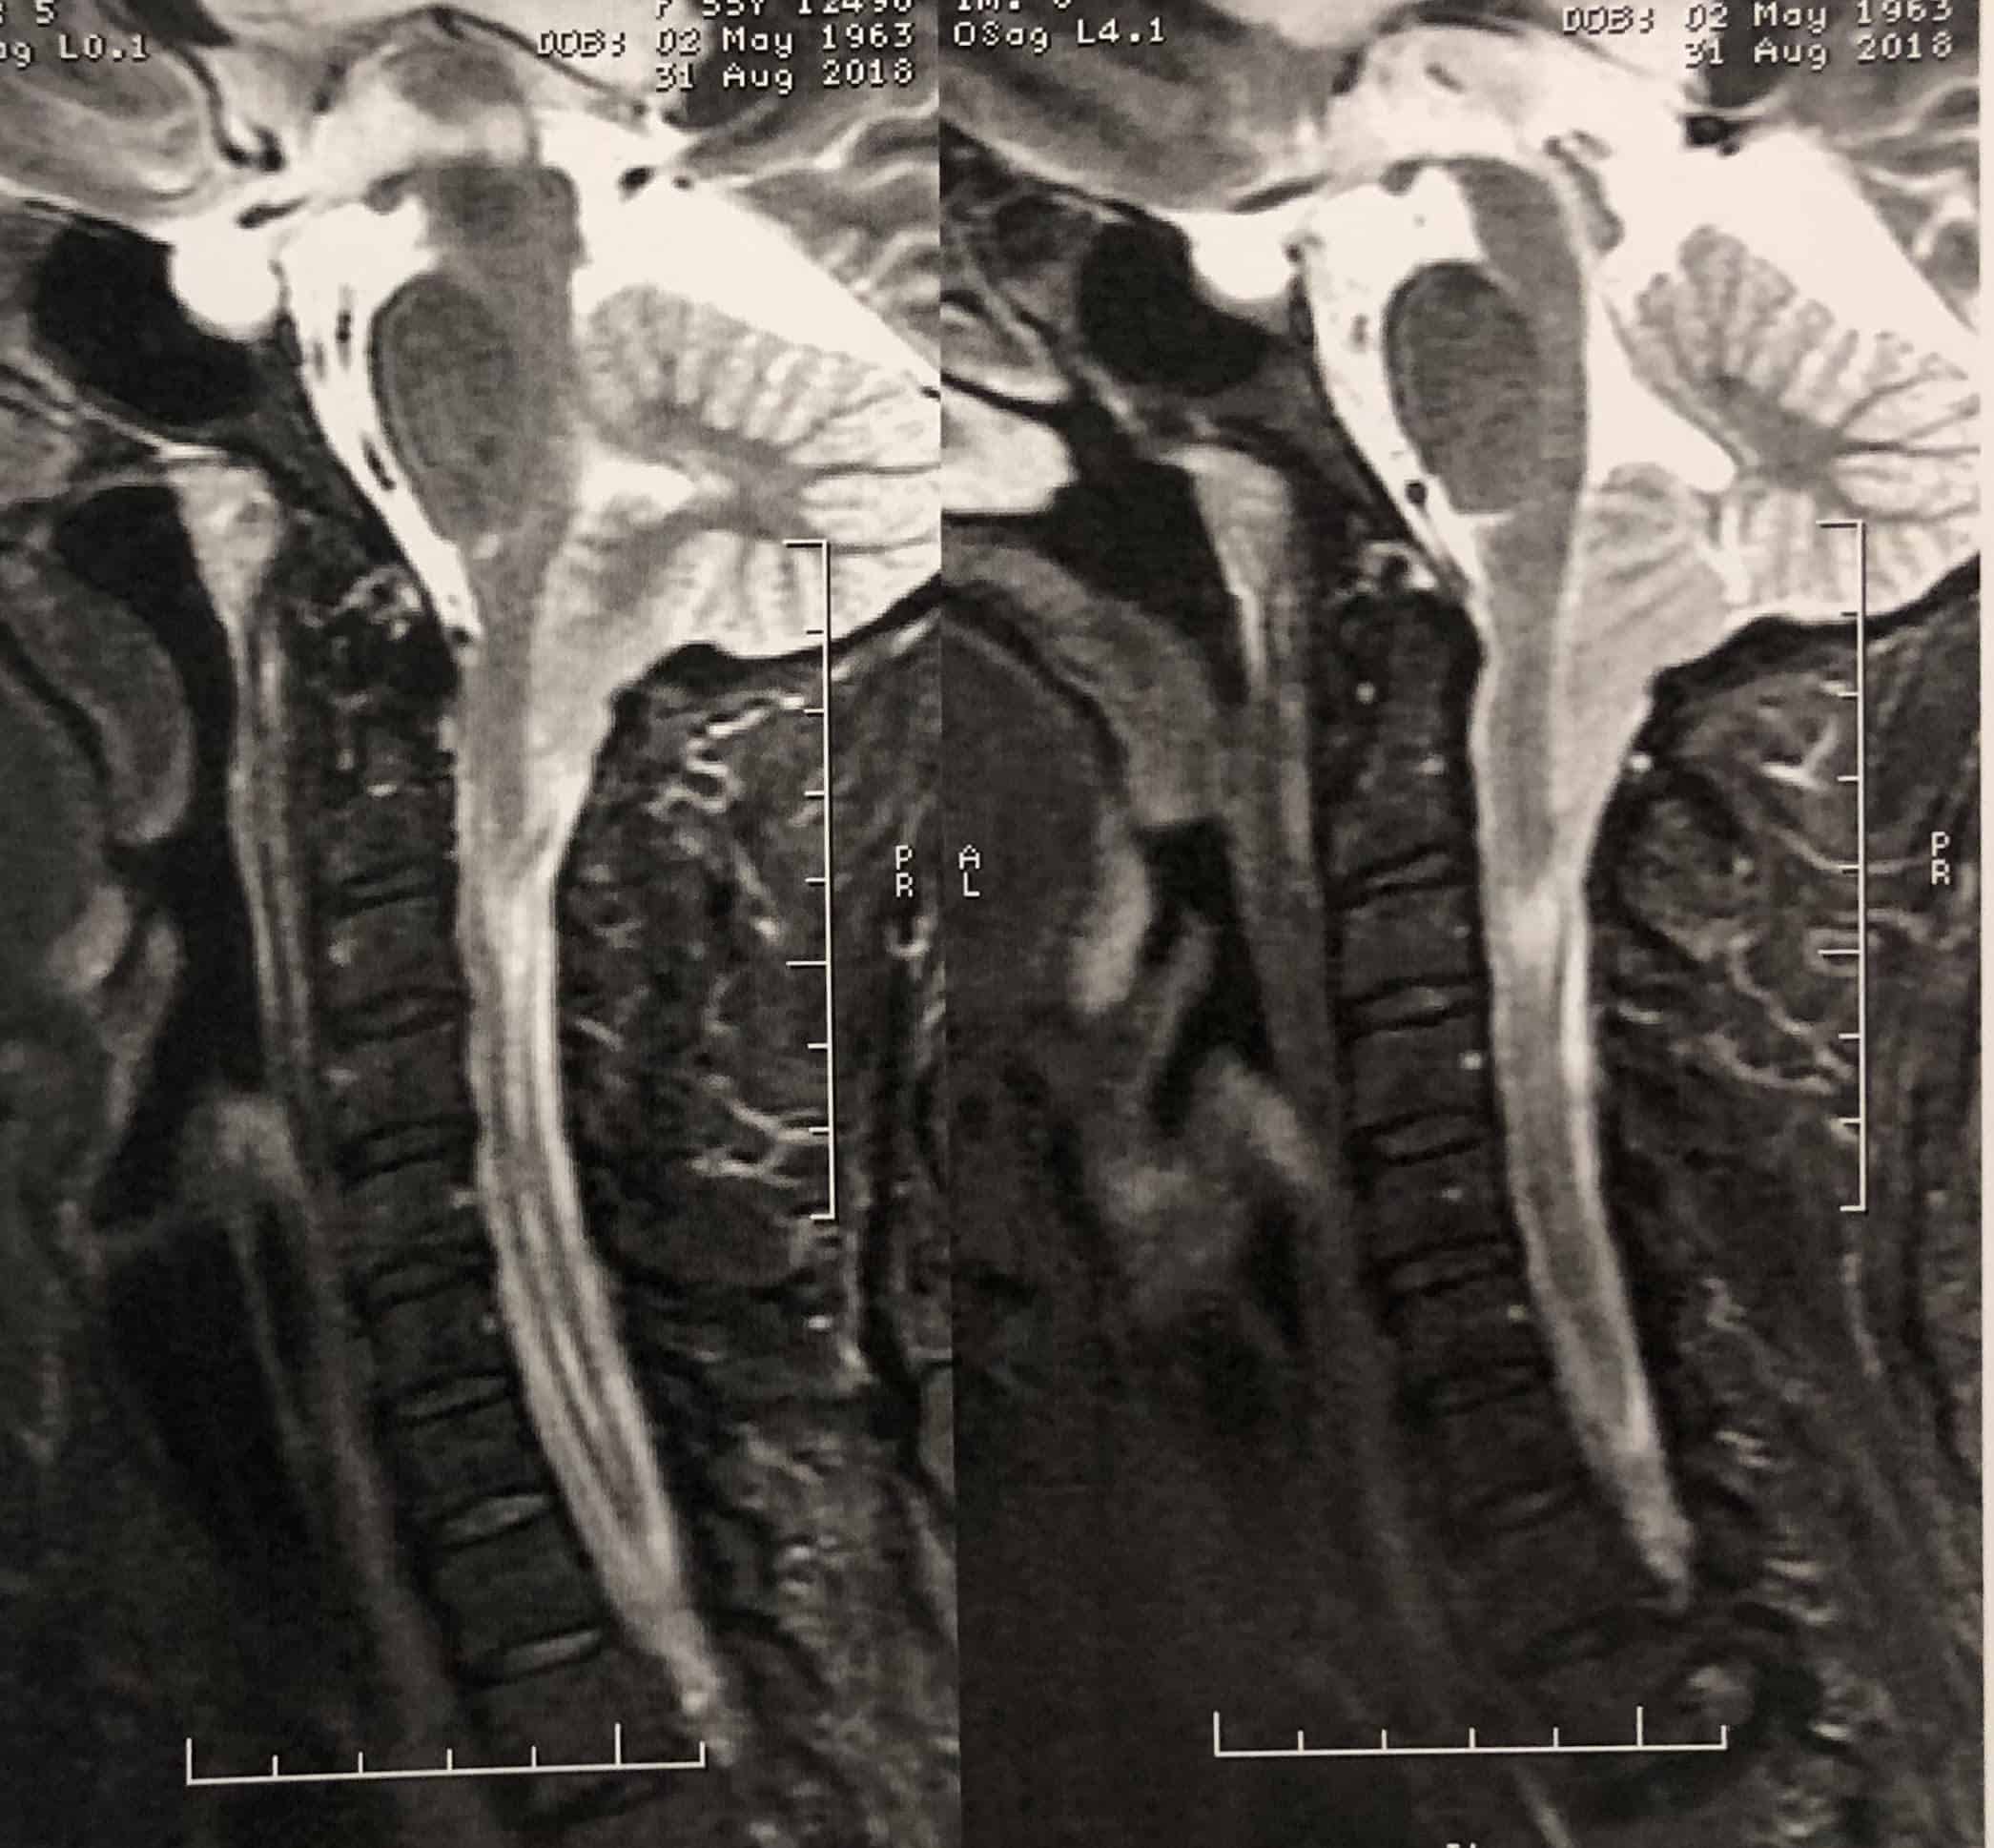

O tipo I geralmente se manifesta entre 30 e 50 anos. É definido como a descida das tonsilas cerebelares através do forame magno (abertura que dá passagem do crânio para a coluna). É mais comum em mulheres e se manifesta como cefaleia (dor de cabeça) na região occipital (nuca), formigamentos nas extremidades, alterações de força nas extremidades e desequilíbrio. O principal sintoma é a dor de cabeça, que se agrava pelo esforço ou tosse.

A malformação de Chiari tipo I pode causar uma alteração medular chamada de siringomielia. Essa é decorrente da obstrução à circulação normal do líquido cefalorradiano nesse segmento, causando a dilatação do canal central da medula. A siringomielia se manifesta por formigamentos, alterações sensitivas e motoras nos níveis abaixo do local alterado. Também podem ocorrer alterações no controle dos esfíncteres com retenção ou incontinência urinária e fecal.